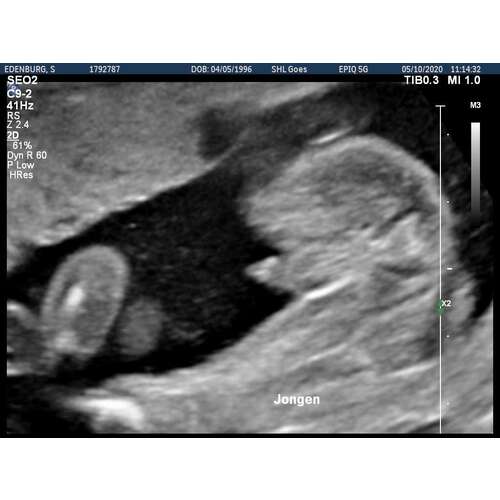

Dit was de 20 weken echo van mijn zoontje. Als ik dat vergelijk met die van jou dan zie ik bij jou toch geen jongen hoor..

Dit was bij ons met 15 wkn. (Jongen)